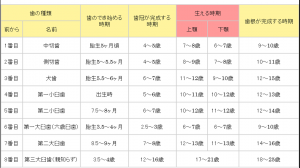

では、歯科の世界はどうでしょうか?

何科があるかご存知でしょうか?

歯科、口腔外科、矯正科、小児歯科はよく診療所に書いてあるのを見るかと思います。